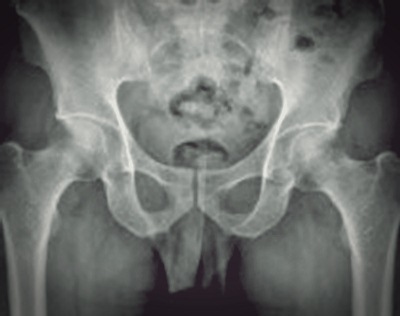

고관절, 구조는

고관절은 우리몸의 187개 관절 중 하나로, 사람에서 가장 큰 관절 중 하나이다. 체중의 1.5에서 최대 10배의 하중을 지탱해주는 역할을 하며 척추와 함께 우리 몸의 기둥 역할을 한다.

고관절의 구조를 보면 재미있는 부분이 있다. 대퇴골두라 불리는 공처럼 둥근 넓적다리뼈의 머리 부분과 이 부분을 감싸는 절구 모양으로 생긴 골반골인 비연구골로 구성되어 있다. 주로 앞뒤로 움직이는 무릎관절과 다르게 고관절의 움직임은 앞뒤, 좌우, 회전 등 움직임의 범위가 넓은 것이 특징이다.

이처럼 골반과 다리를 연결해주며, 체중 지탱과 함께 보행을 돕는 핵심적인 역할을 하기 때문에 그 구조가 안정적이다. 이런 안정적인 구조에도 불구하고 고관절 건강을 챙기지 않으면 고관절 충돌 증후군 등 관절 질환을 호소할 수 있다.

첫째, 음주가 가장 큰 영향을 미치는 대퇴골두 무혈성괴사가 있다. 대퇴골두의 혈액 공급이 차단되면서 골두 부위의 뼈가 괴사 하는 질환이다. 두 번째는 선천성이나 퇴행성, 류미티스를 포함한 외상에 의한 감염 등으로 관절의 연골이 닳아 없어지는 고관절염이 있다. 마지막으로 고관절 충돌 증후군은 관절 가장자리 위치에서 뼈끼리 부딪히며 유발되는 통증으로 과도한 운동이나 움직임으로 우리 생활 속에서 쉽게 나타날 수 있다.